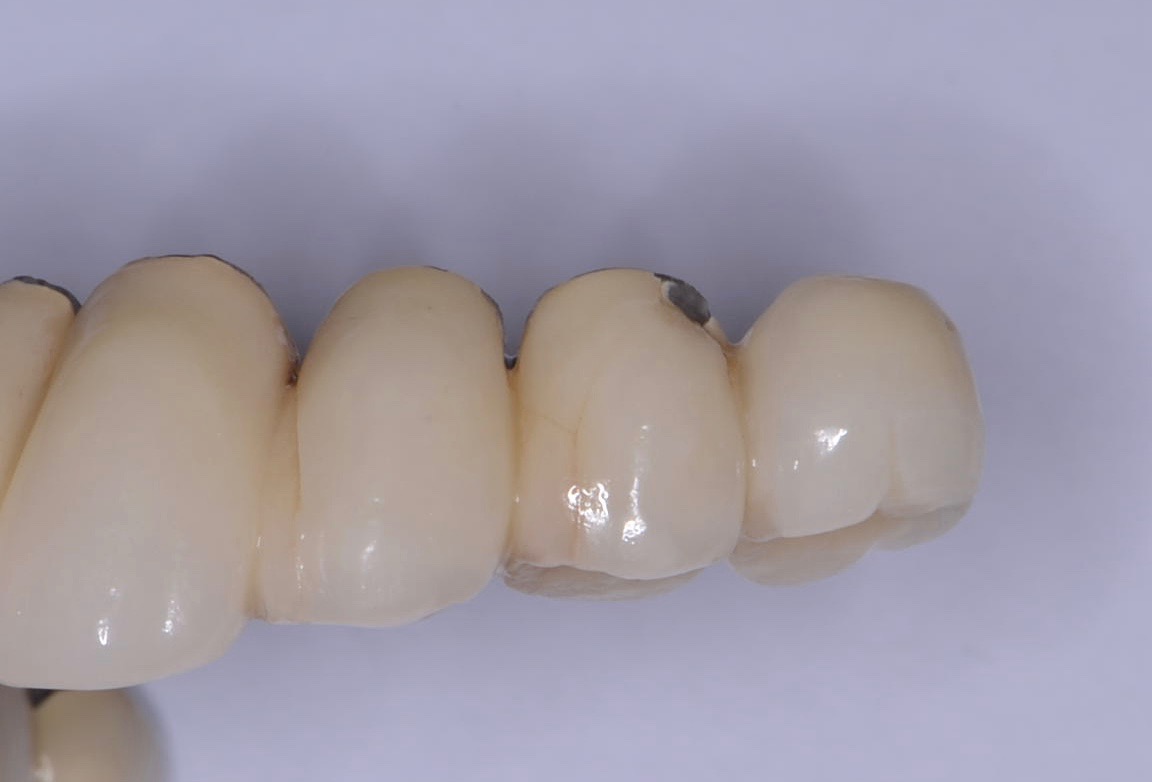

Fig 1. Chipping of veneering porcelain of porcelain-fused-to-gold full-arch fixed dental prosthesis.

Figure 1

Fracture/Chipping of the Veneering Material

With 5-year complication rates from 3.2% to 25.5%,1 chipping of the veneering material (Figure 1) is the most common technical complication addressed in the literature.1,2 This can be minimized by designing the prosthesis before the final fabrication to ensure optimal framework design and thickness of the veneering material. Following basic occlusal principles in implant prosthodontics is essential. These include reduced cuspal inclination, narrow occlusal table, correction of load direction, reduced nonaxial loading, reduced length of the cantilever, and lighter occlusal contacts on implants.5 Restorations such as monolithic zirconia (Figure 2) and lithium disilicate are also being used to minimize chipping. However, long-term follow-up information on these restorations is limited.